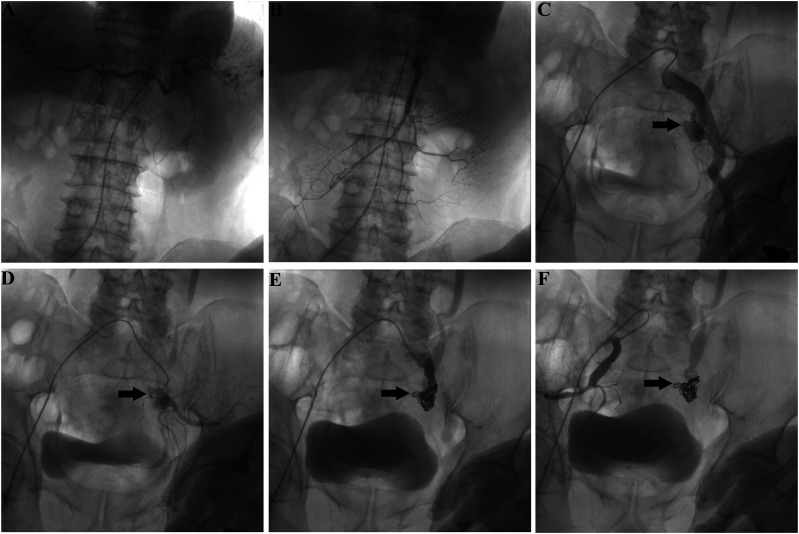

Primary aortoenteric fistula is a rare entity with high mortality. Depending on the location of the fistula, primary aortoenteric fistulas may lead to upper or lower gastrointestinal hemorrhages. The majority of primary aortoenteric fistulas are associated with atherosclerosis or aneurysms of the aorta, without any previous aortic procedure. Local inflammation, compression, or erosion may lead to rupture of the aneurysm. Owing to difficulties in immediate and correct diagnosis, effective treatment of primary aortoenteric fistulas is often delayed, leading to almost 100% mortality in untreated patients. Here, we report a case of a repetitive mass of lower gastrointestinal hemorrhage due to a primary internal iliac arterial-sigmoid colon fistula. Finally, the patient was managed successfully through endovascular coil embolization.